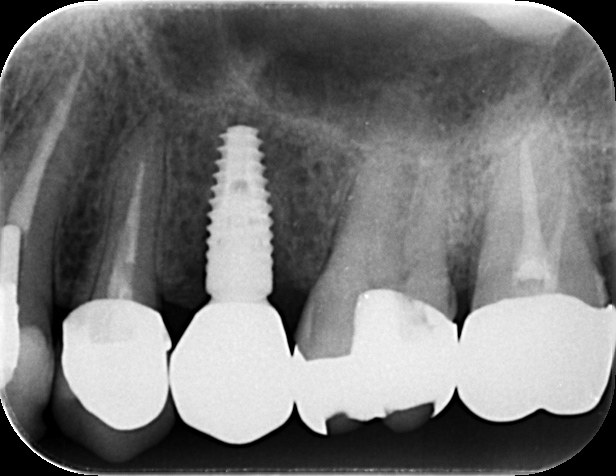

レントゲンおよびCT撮影に加え、マイクロスコープ(歯科用顕微鏡)を用いて患部を詳細に確認しました。

他院での根管治療歴がある左上5番ですが、マイクロスコープでの視診において、歯の根元に「破折(はせつ)」、つまりヒビが入っていることが確認されました。また、そのヒビが原因となり細菌感染が広がり、根っこの先に膿が溜まる「根尖病変(こんせんびょうへん)」も認められました。

しかし、今回の患者さんは口腔内環境が比較的良好であり、既存の骨の状態も悪くありませんでした。そこで当院では、抜歯をしたその日のうちにインプラントを埋入する「抜歯即時インプラント」を計画しました。

1.データ取得: CT画像(骨の情報)と、3Dスキャン(歯ぐきや歯並びの情報)を取得。

2.マッチング: 2つのデータを重ね合わせ、コンピュータ上で手術のシミュレーションを行います。

しかし今回は、抜歯した穴(抜歯窩)をそのまま利用してインプラントを固定できたため、大掛かりな骨造成を回避することができました。